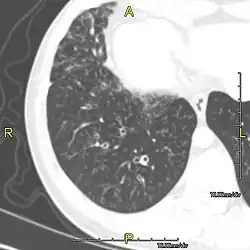

Around 80% of people with primary ciliary dyskinesia experience respiratory problems beginning within a day of birth. Many have a collapsed lobe of the lung and blood oxygen low enough to require treatment with supplemental oxygen.[1] Within the first few months of life, most develop a chronic mucus-producing cough and runny nose.[1] The main consequence of impaired ciliary function is reduced or absent mucus clearance from the lungs, and susceptibility to chronic recurrent respiratory infections, including sinusitis, bronchitis, pneumonia, and otitis media. Progressive damage to the respiratory system is common, including progressive bronchiectasis beginning in early childhood, and sinus disease (sometimes becoming severe in adults). However, diagnosis is often missed early in life despite the characteristic signs and symptoms.[2] In males, immotility of sperm can lead to infertility, although conception remains possible through the use of in vitro fertilization, there also are reported cases where sperm were able to move.[8] Trials have also shown that there is a marked reduction in fertility in females with Kartagener's syndrome due to dysfunction of the oviductal cilia.[9]

Many affected individuals experience hearing loss and show symptoms of otitis media which demonstrates variable responsiveness to the insertion of myringotomy tubes or grommets. Some patients have a poor sense of smell, which is believed to accompany high mucus production in the sinuses (although others report normal – or even acute – sensitivity to smell and taste). Clinical progression of the disease is variable, with lung transplantation required in severe cases. Susceptibility to infections can be drastically reduced by an early diagnosis. Treatment with various chest physiotherapy techniques has been observed to reduce the incidence of lung infection and to slow the progression of bronchiectasis dramatically. Aggressive treatment of sinus disease beginning at an early age is believed to slow long-term sinus damage (although this has not yet been adequately documented). Aggressive measures to enhance clearance of mucus, prevent respiratory infections, and treat bacterial superinfections have been observed to slow lung-disease progression. The predicted incidence is 1 in approximately 7500.[10]

When accompanied by the combination of situs inversus (reversal of the internal organs), chronic sinusitis, and bronchiectasis, it is known as Kartagener syndrome[3] (only 50% of primary ciliary dyskinesia cases include situs inversus).[11]